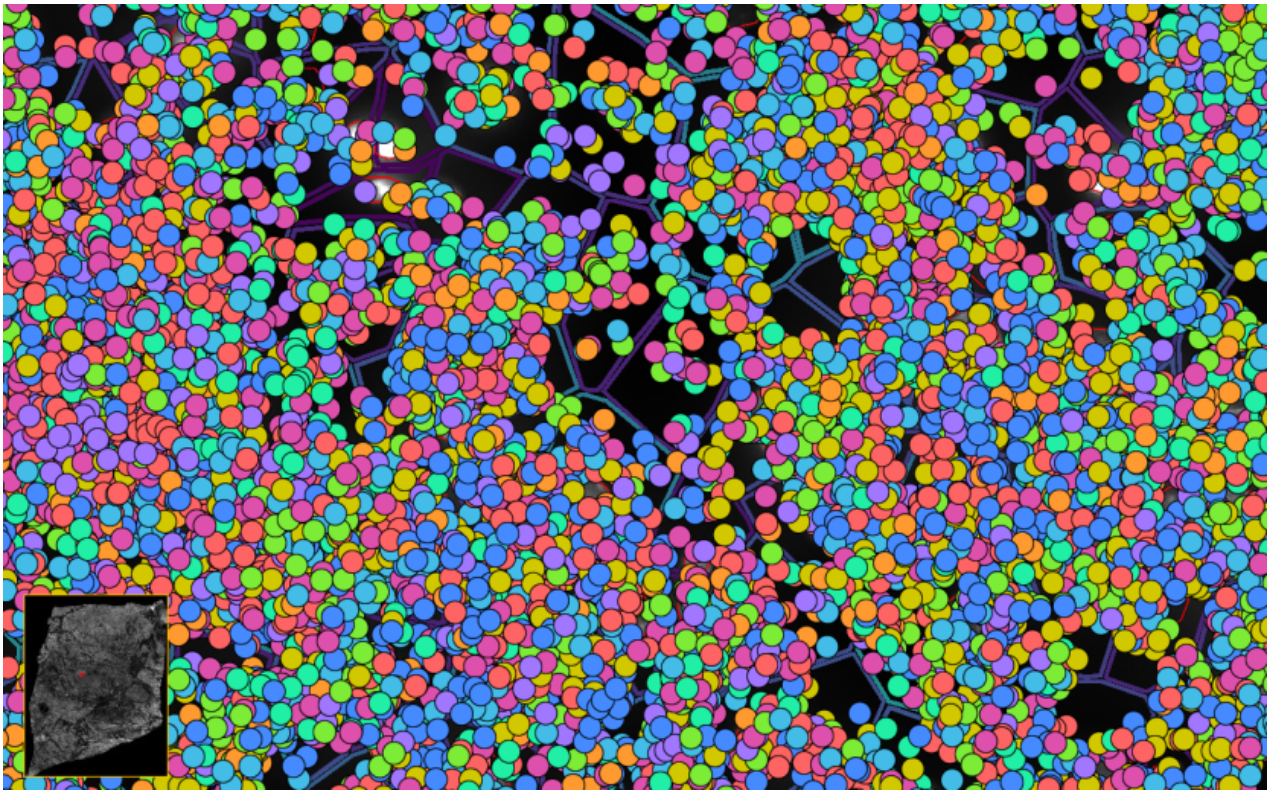

ͼ5£º½«×ªÂ¼ÌìÖ°Åä¸øÏ¸°û